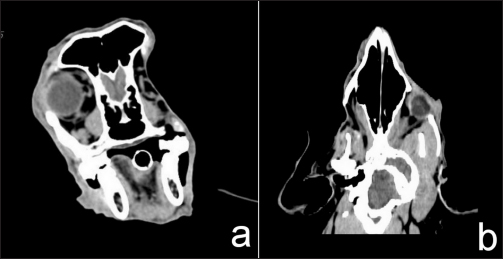

CT for 4 weeks after the surgery demonstrated a heterogeneous mass effect (0.6 × 0.8 cm) in the right caudal maxilla area which extended to part of the right retrobulbar mass with hyper density contrast enhancement (Fig. 4). There was no detection of soft-tissue nodules in the lungs. The radiation treatment plan aimed to control retained mass and micro metastasis.

Fig. 4. Transverse (a) and dorsal (b) computed tomographic images in the right retrobulbar, maxilla, zygomatic, and temporal areas with mass effect at right caudal maxilla area, extending to part of right retrobulbar mass with hyper density contrast enhancement.